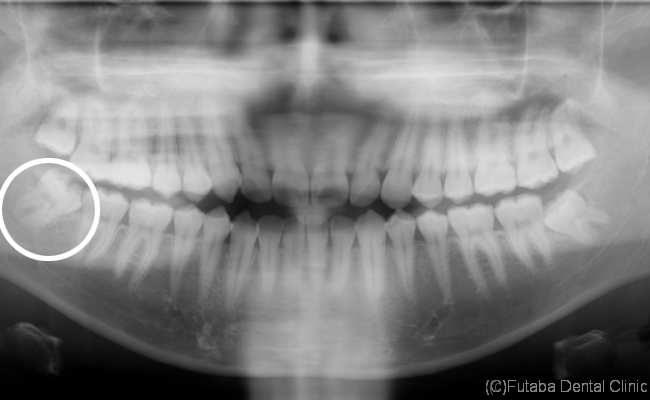

現代の人は、顎が小さくなってしまった為、

親知らずがきれいに萌出できない場合があります。

その場合、顎の中に完全に埋まっている場合、

少しだけ、頭を出している場合など

色々な状態があります。

今回は、頭は出ているが、萌出するスペースがない為

手前に倒れた状態で、生えています。

しかも、手前の歯に接触している為

手前の歯を前方へ押してしまい、

前歯の歯並びが乱れる原因の一つになってしまいます。